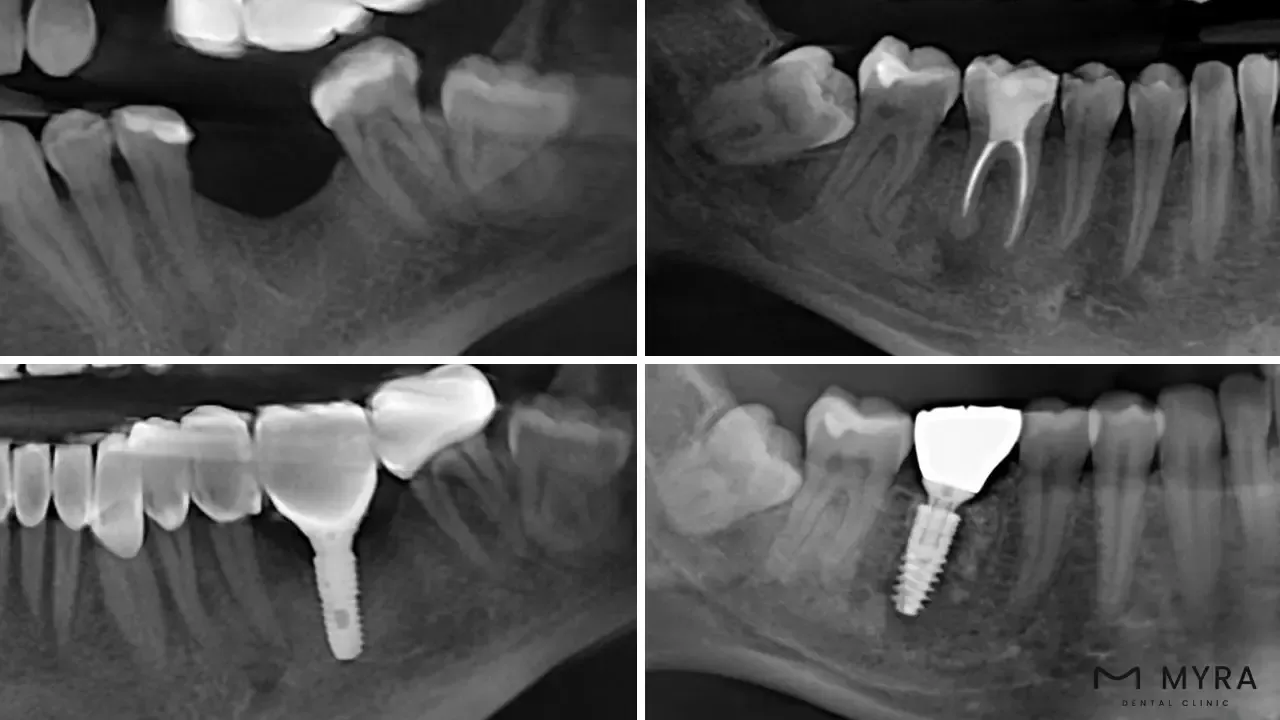

Condition of the dental bones: A sufficient amount of bone is necessary because insufficient bone is potential to compromise implant stability which result in recession, loss of papilla, and improper alignment. Dentists opt to use regenerative treatments, such as guided bone regeneration, orthodontics, and/or grafting, during the first stage of treatment when the quality and quantity of the bone are insufficient. Dental exams are crucial to determining the health of the dental bones prior to placing an instantaneous load implant. These evaluations provide dentists the chance to spot any existing oral issues that are potential to lower the success percentage of the implant. It must be examined to make sure the dental bone's framework is able to withstand a sudden load implant. The evaluation normally consists of a thorough dental examination, which often involves X-rays, 3D scans, and models of the patient's teeth and jaws. The dental bone structure plays the most role in whether or not an instant load implant is going to be successful. The quantity and quality of the bone must be assessed in order to decide whether the implant is successfully implanted. The implant has the potential to malfunction if the bone is not dense enough to handle the strain of chewing. A bone transplant sometimes requires fortification of the bone prior to implant placement in some circumstances. The dentist assesses the patient's overall dental health, medical history, and lifestyle choices before determining whether a bone graft is required. Dental examinations prior to an instant load implant are essential for assuring a successful and long-lasting implant, in general. Dentists create a customized treatment plan that caters to the patient's specific needs and assures the optimum outcome by diagnosing any pre-existing dental issues and assessing the dental bone structure.

The process of an immediate load dental implant installation takes a few steps. Immediate load dental implants are a particular kind of implant treatment in which a dental prosthesis is attached to the implant right away after it has been placed. Immediate loaded implants are usually inserted into the hard bone layer that lies above the porous bone. The layer of hard bone offers an instant, secure platform for the crowns and bridges while the implants progressively bond with the spongy bone.

The jawbone is made ready to accommodate the fixture of the dental implant. The implant is drilled through the jawbone, into the porous bone, and down into the lowest layer where the hard bone is situated. The hard bone provides a quick and strong foundation for the prosthesis, while the implants gradually integrate with the porous bone at the same time.

The period of time necessary for the implant to integrate or bind with the jawbone called osseointegration is then specified. The implant dentist uses optical scans or molds of the patient's mouth to create custom replacement teeth for them. The comfort of new teeth is experienced in a few quick appointments.